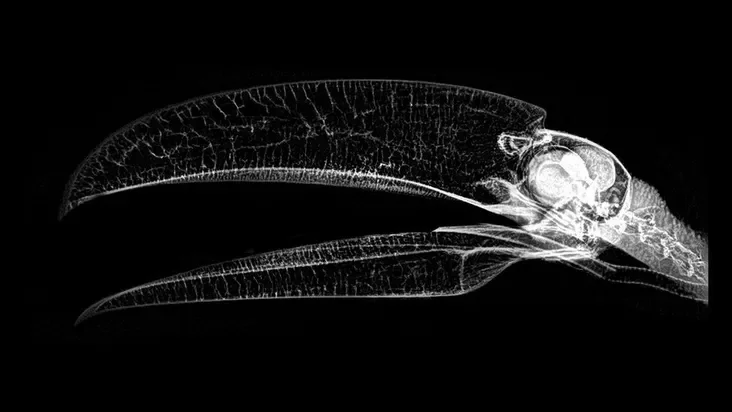

Зоопарк в американском штате Орегон опубликовал рентгеновские снимки своих животных. Их сделали во время медосмотра.

По словам представителей зоопарка, рентген — один из самых эффективных методов диагностики у животных. Кроме того, он позволяет минимизировать время анестезии при операциях.

Такие снимки редко обнародуют, поскольку их делают исключительно в исследовательских целях.

Большой тукан.